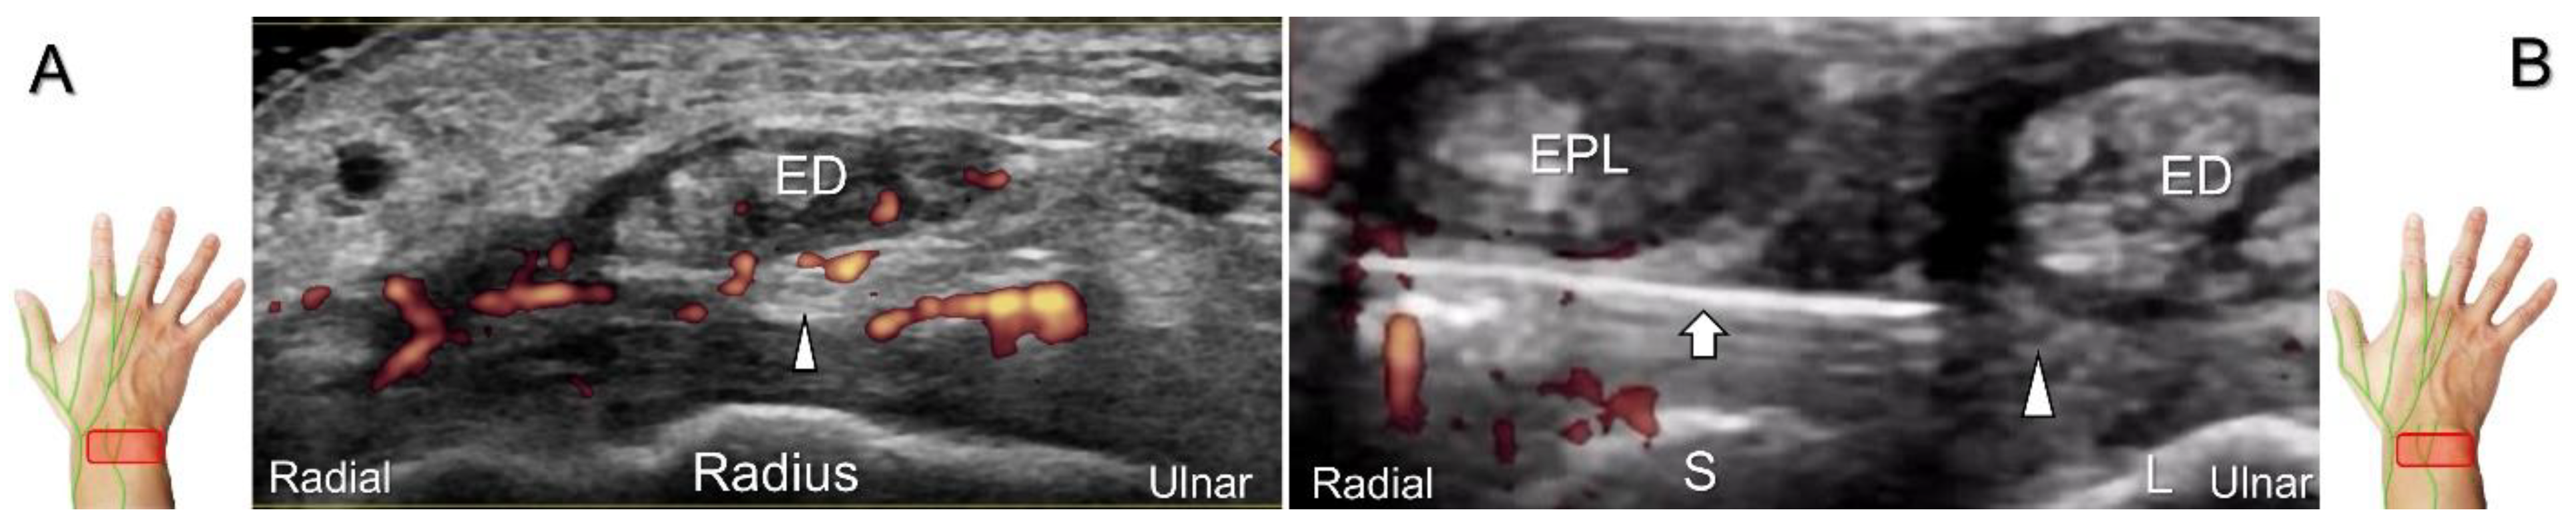

With the forearm supinated, the transducer is placed at the radial side of the upper third of the forearm in short-axis view. The posterior interosseus nerve is situated between the extensor digitorum longus and abductor pollicis longus (or extensor pollicis brevis) muscles. The transducer is moved distally along the dorsal forearm. The nerve courses radial to the extensor pollicis longus muscle and then dives toward the surface of the dorsal interosseous membrane. At the wrist level, the nerve appears as a small hypoechoic monofascicle with an average diameter about 1–3 mm [46] and then it travels onto the carpus with the dorsal interosseous artery (Figure 26A).

Clinical Implication

Nerve entrapment can occur from repetitive and forceful use of extensor digitorum longus and extensor pollicis longus muscles. Contusion to the wrist can traumatize the posterior interosseus nerve, leading to neuroma formation (Figure 26B,C). The nerve can also be irritated by hypertrophic synovium secondary to extensor digitorum communis tenosynovitis (Figure 27A) [47]. When injecting the scapho-lunate joint, the nerve should be identified first to avoid iatrogenic injury. In cases suffering from pain or allodynia over the dorsal radioulnar joint, hydrodissection of the nerve can be performed. The in-plane approach during the nerve’s short-axis view is the preferred method (Figure 27B) whereby iatrogenic injury of the vessels and extensor tendons can be prevented.

Figure 26. Sonographic imaging (short-axis view) of the dorsal interosseus nerve from the normal (A) to the swollen (B) segment proximal to the entrapment site. Normal, swollen, and compressed segments of the nerve are seen in long-axis view (C). White arrowhead: normal segment; black arrowhead: swollen segment; yellow arrowhead: entrapped segment; EPL: extensor pollicis longus tendon; ED: extensor digitorum tendon.

Diagnostics 13 01928 g026

Figure 27. Sonographic imaging (short-axis view) is performed to assess the posterior interosseus nerve entrapment due to synovitis in rheumatoid arthritis (A). Ultrasound-guided injection (B). Arrowheads: posterior interosseus nerve; arrow: needle; EPL: extensor pollicis longus tendon; ED: extensor digitorum communis tendon; S: scaphoid; L: lunate.

Diagnostics 13 01928 g027